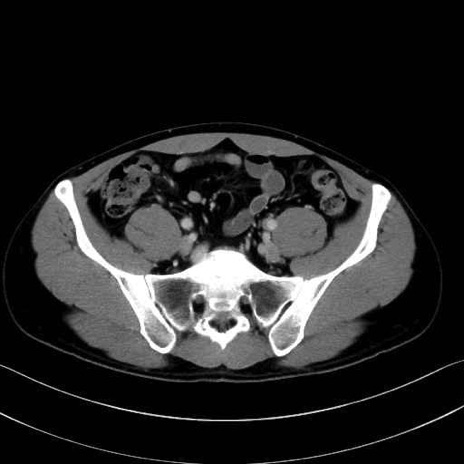

小殿筋 (Gluteus minimus)